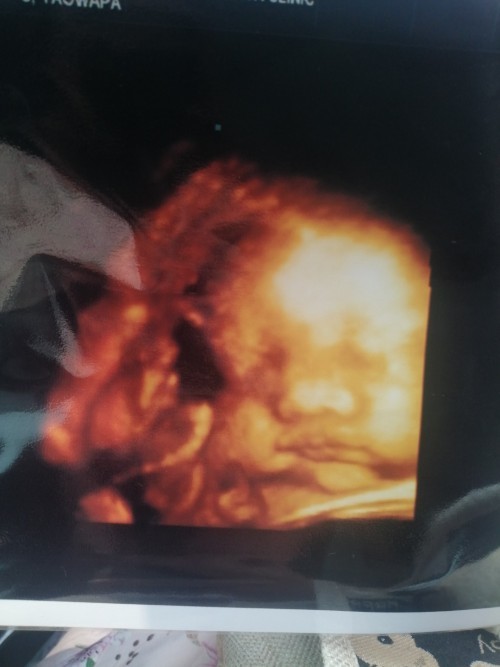

ขอดูภาพซาวด์4มิติ ของแม่ๆท่านอื่นหน่อยคะ บ้านนี้ซาวด์ปัยน้องยิ้มเล่นไปด้วย ให้ทายว่าน้องเปนผญ.หรือผช.😊

หนุเป็นเด็กผุ้ชายคับแม่ๆ 32+5w